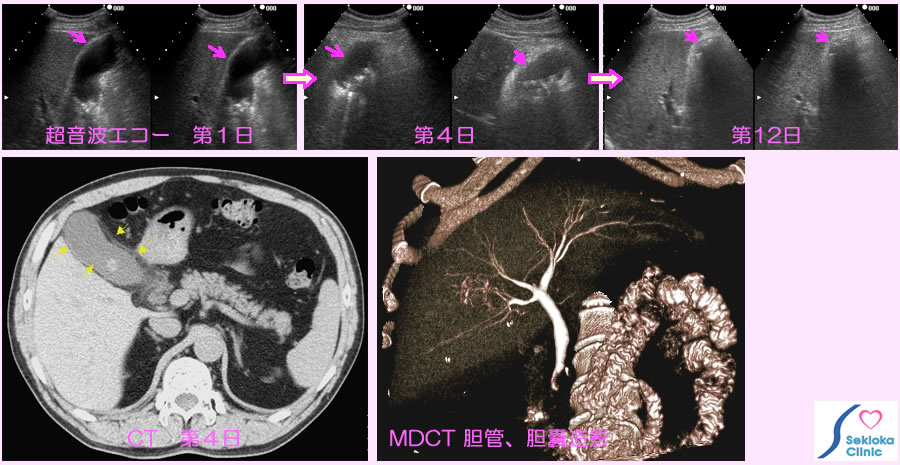

| 診断 | お腹の触診、超音波エコー検査、血液生化学検査、CTなど。上段の超音波エコー検査では来院時、胆嚢は腫大し、胆石を認めます。下段は4日目のCT画像。手術方法を検討する際、胆管内に胆石が存在するか否かは重要です。胆管、胆管内胆石診断のため 造影MDCTで胆管、胆嚢造影を行ったものが下段右の画像です。本例は有意な胆管拡張、胆石による陰影欠損は認めません。 |

| 治療 | 抗生剤の点滴、内服。食事は控える。または絶食。上段の超音波エコー画像は胆嚢の経時的変化を示します。12日目のエコー画像では胆嚢の腫大は消失しています。外来で、抗生剤の点滴を朝夕行い、3日目から自覚症状の改善、血液検査値の改善を認め、その後順調に経過しました。 |